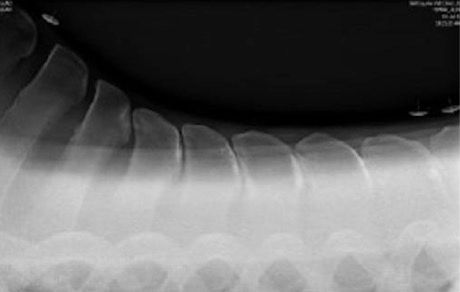

The x-rays below show no gaps in places, so every time this particular horse, has a rider's weight on those areas shown, are asked to turn on a circle or work or simply just carry a rider they probably will feel quite a bit of pain and therefore will show signs of that pain.

Ruling out Kissing Spines is very easy – A set of x-rays will give you the answer you need, but use an experienced vet who can

read the images well and who will understand that the vertebral bodies below the Kissing Spine area (called Facet Joints) also

need to be looked at to eliminate any doubt of pain from this part of the spine too.